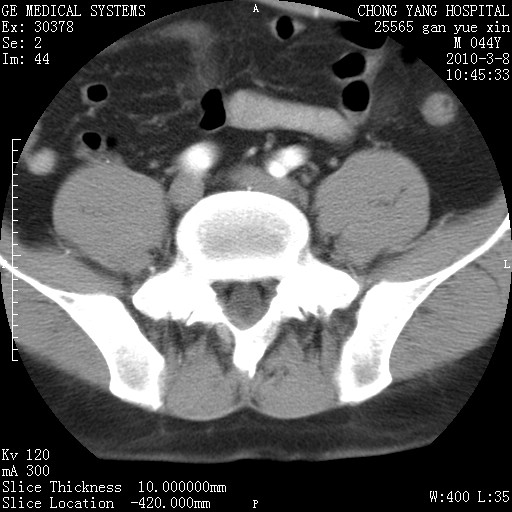

标题: CT24940:主动脉增强,典型病例。 [打印本页]

标题: CT24940:主动脉增强,典型病例。

夹层动脉瘤。

动脉夹层

夹层动脉瘤,典型

主动脉夹层。

动脉夹层的分型:

⒈debakey分型:根据主动脉夹层累及部位,分为三型:ⅰ型:原发破口位于升主动脉或主动脉弓部,夹层累及升主动脉、主动脉弓部、胸主动脉、腹主动脉大部或全部,少数可累及髂动脉。ⅱ型:原发破口位于升主动脉,夹层累及升主动脉,少数可累及部分主动脉弓。ⅲ型:原发破口位于左锁骨下动脉开口远端,根据夹层累及范围又分为ⅲa,ⅲb。ⅲa型:夹层累及胸主动脉。ⅲb型:夹层累及升主动脉、腹主动脉大部或全部。少数可累及髂动脉。

⒉stanford分型:a型:夹层累及升主动脉,无论远端范围如何。b型:夹层累及左锁骨下动脉开口以远的降主动脉。

夹层动脉瘤,少量胸水

夹层动脉瘤;左侧少量胸腔积液。

典型主动脉夹层。